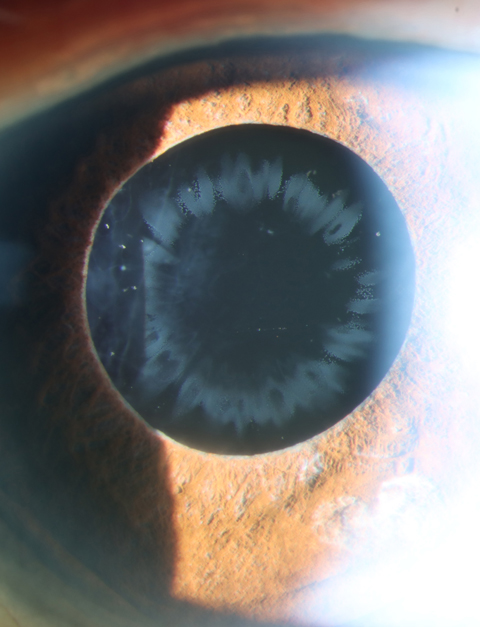

Persistent pupillary membrane type 2